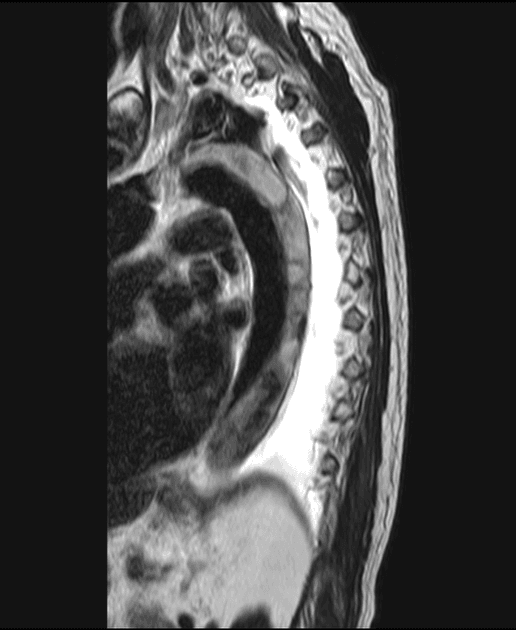

Nhiều tổn thương bắt thuốc trong màng cứng dọc theo cột sống cổ - ngực.

Hình ảnh tương tự như các tổn thương trong não.

Khối u thần kinh đặc trưng là u mạch máu nhân dạng tế bào (hemangioblastoma), có thể xuất hiện ở não hoặc tủy sống.

- "U mạch máu trong VHL thường đa ổ và có thể xảy ra ở tiểu não, thân não và tủy sống."